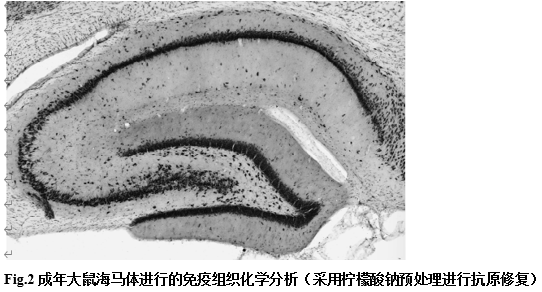

产品应用实例: